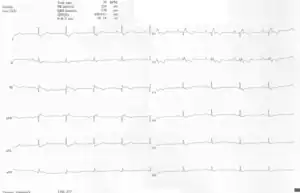

A 10-lead ECG of a woman with Ebstein's anomaly: The ECG shows signs of right atrial enlargement, best seen in V1. Other P waves are broad and tall, these are termed "Himalayan" P waves. Also, a right bundle-branch block pattern and a first-degree atrioventricular block (prolonged PR-interval) due to intra-atrial conduction delay are seen. No evidence of a Kent-bundle is seen in this patient. The T wave inversion in V1-4 and a marked Q wave in III occur; these changes are characteristic for Ebstein's anomaly and do not reflect ischemic ECG changes in this patient.